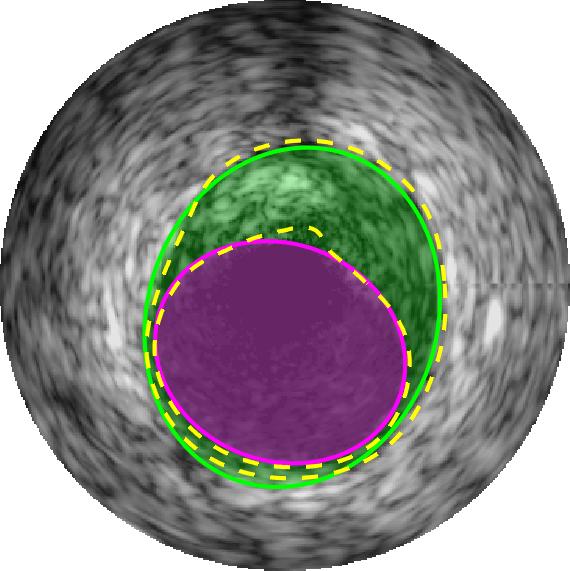

Qualitative evaluations are illustrated in Figure 4 and show the successful segmentation results of the proposed EREL selection strategy for 20 IVUS frames. The lumen areas are highlighted by the magenta colour while the media regions are green. Also, the manually annotated contours for both lumen and media are drawn as yellow dashed lines. As we can see, the chosen frames contain a variety of lumen and media morphologies.